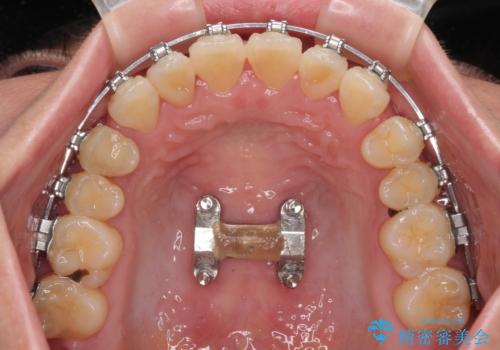

上顎の急速拡大装置を使用して上顎骨を側方に拡大することで上顎歯列を拡大し、下顎歯列も拡大できるようにすることで、歯列を整えることとしました。

歯列矯正では基本的に骨格を改善することはできませんが、急速拡大装置(MARPE)を使用することで上顎骨を側方に拡大させることができ、咬合状態を大きく改善することができます。